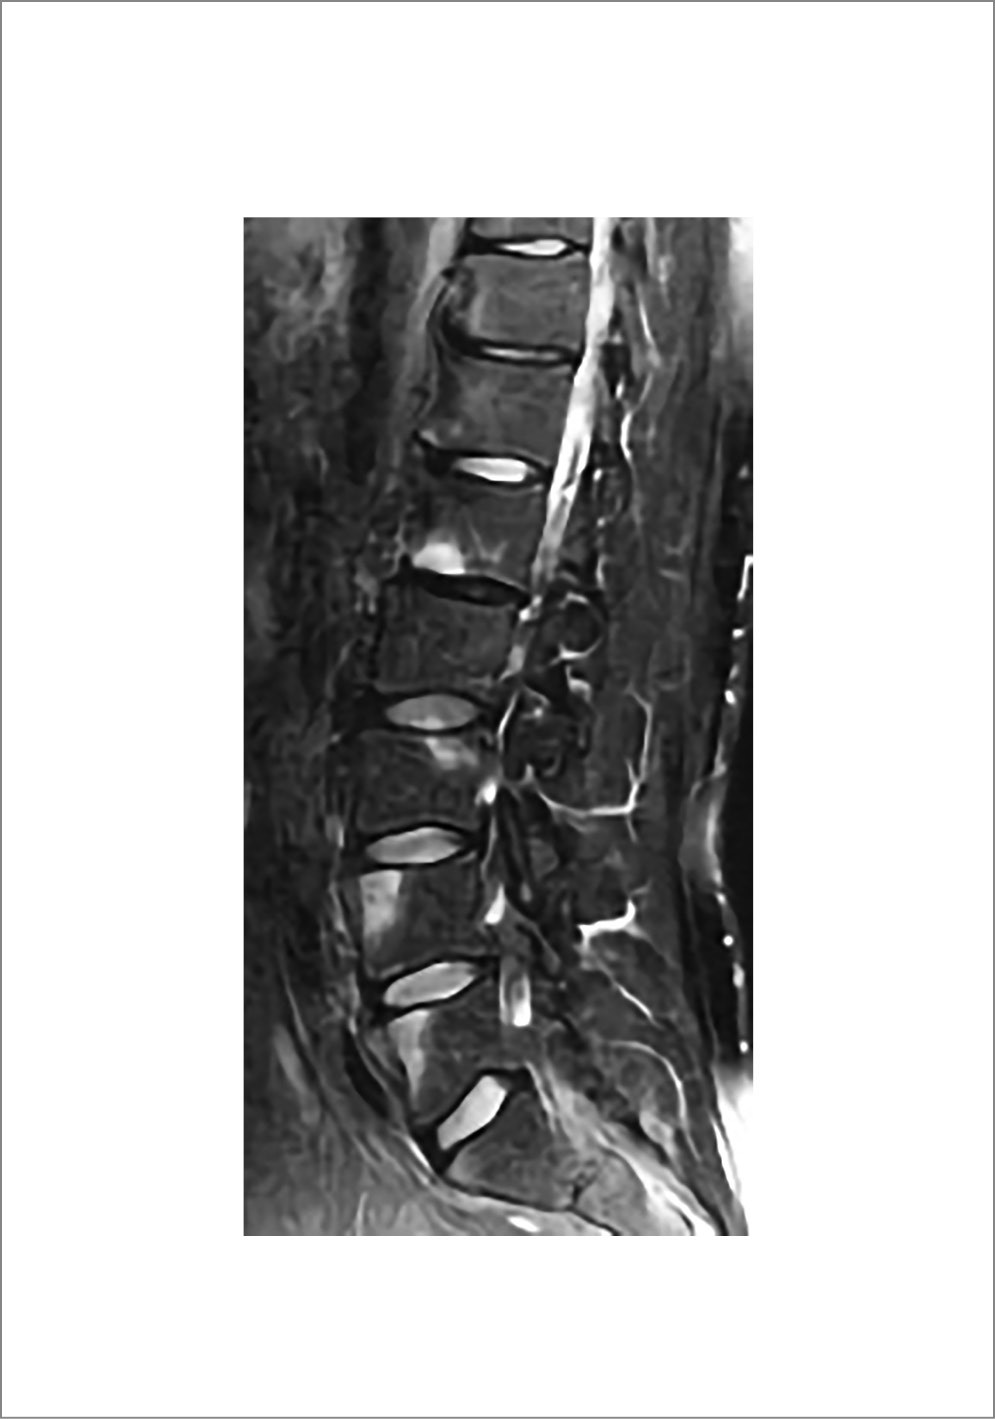

. Он вызывается деструкцией межпозвонкового диска и замыкательных костных пластинок тел позвонков, прилегающих к пораженному диску. Отмечаются локальное или распространенное сужение межпозвонкового промежутка, дефекты (неровности) поверхностей тел, соседствующих с диском, и широкие зоны остеосклероза. Спондилодисцит чаще обнаруживается в нижнегрудном и верхнепоясничном отделах. Размеры деструкции дисковых поверхностей тел варьируют от нескольких миллиметров в ширину и глубину, когда имеется сходство с грыжами Шморля, до значительных, с распространением на всю или почти всю верхнюю или нижнюю поверхность тела позвонка. В последних случаях в генезе спондилодисцита основную роль может играть не воспаление, а локальная травма вследствие избыточной подвижности позвоночника в данном сегменте, к которой предрасполагает анкилозирование выше и ниже расположенных структур. Значительная деструкция приводит к так называемому вертебральному псевдоостеоартрозу. Небольшие деструктивные изменения позвонков при АС могут быть бессимптомны или малосимптомны. Спондилодисцит отчетливо визуализируется на МРТ. Характерны дискообразный отек тел позвонков по обе стороны пораженного диска, сужение межпозвонкового промежутка, нередко отек, неровности и эрозии замыкательных костных пластинок позвонков, прилегающих к поврежденному диску (рис. 4) [3].

Рис. 4. Пациент Г., 40 лет. Диагноз – АС, длительность болезни – 20 лет. МРТ грудного отдела позвоночника (сагиттальная плоскость, режим T2-FS): зоны отека в телах ThXI–ThXII позвонков, смежные замыкательные пластики их узурированы, высота диска между ними увеличена, сигнал его структуры неоднородно повышен (спондилодисцит).